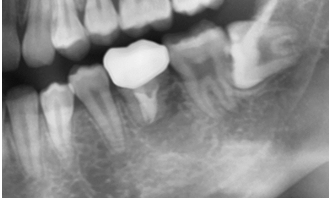

治療前:牙根尖發炎

治療前X光片

治療完成X光片